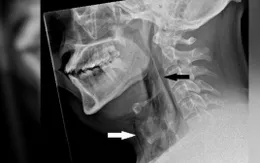

Ghi nhận trường hợp "rách khí quản vì nhịn hắt hơi" đầu tiên trên thế giới

VTV.vn - Nếu bạn thường xuyên nhịn hắt hơi, trường hợp hy hữu sau đây có thể là lời cảnh báo dành cho bạn.